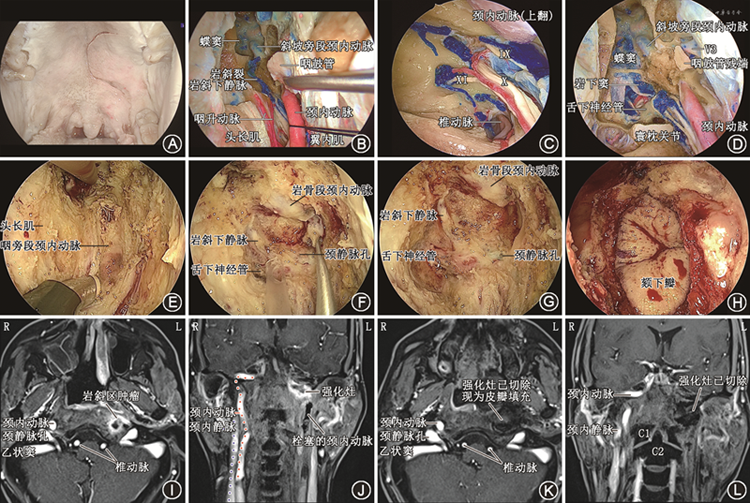

2. 内镜经口经翼下颌皱襞入路(侧方入路):内镜经口经翼下颌皱襞入路适用于病变主体位于侧方咽鼓管区和神经血管区的病变[5, 6],如咽后淋巴结、咽旁间隙肿瘤等。该入路的切口位于翼下颌皱襞内侧黏膜,进一步切开咽上缩肌后进入咽旁前间隙。定位咽旁段颈内动脉是内镜经口经翼下颌皱襞入路的核心。茎突咽筋膜位于茎突至咽上缩肌的三角区域,去除茎突咽筋膜,从内向外依次可见头长肌、咽升动脉、颈内动脉和颈内静脉。腭帆提肌位于该入路术腔的上部,其外上方的附着点位于颈内动脉外口前方,可作为颈内动脉外口定位的标志(图5)。

3. 内镜经口翼突后入路(联合入路):内镜经口翼突后入路适用于病变广泛侵犯颅底中线区域和侧方区域的病变,如晚期的复发性鼻咽癌、颅底恶性肿瘤等。该入路经口行大问号切口。切开咽上缩肌进入咽旁间隙,通过茎突肌群定位咽旁段颈内动脉,确定安全边界。在经鼻入路中,需要磨除翼突才能自前向后显露上述解剖结构。而在内镜经口翼突后入路中,在翼内肌和咽上缩肌之间通过下咽旁间隙至翼突后,从翼突后方即可显露上述解剖结构。避开翼突,通过咽旁间隙这一固有解剖间隙直达颅底,不仅创伤小、出血少、省时省力,而且因为保留了翼内肌和翼外肌,可以最大化地保护患者的咀嚼功能。该入路以最直接的径路到达岩斜区、颈静脉孔区,在确保风险可控的前提下,可以最大范围地显露岩斜区和颈静脉孔区,同时最大程度地保护翼内肌和翼外肌(图6)。

3. 神经血管区:在咽鼓管区后方,由颈内动脉管外口、颈静脉孔、舌下神经孔和茎乳孔共4个颅底孔道构成。经颞骨岩部的颈动脉管外口进入颈动脉管。内镜经口入路中,可借助咽鼓管和腭帆提肌定位颈动脉管外口。